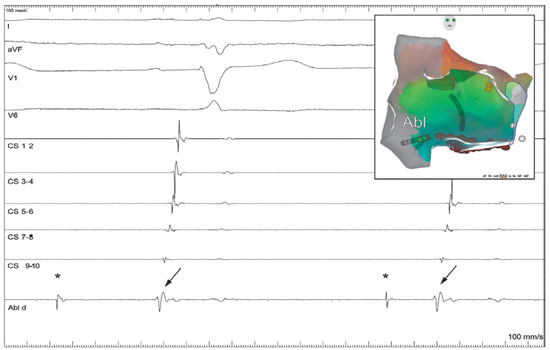

The Eustachian ridge is ablated as part of the cavotricuspid isthmus (CTI) involved in typical atrial flutter (AFL) ablation, but is itself rarely an arrhythmogenic focus. We report a case of a patient with dual tachycardia involving the CTI area....